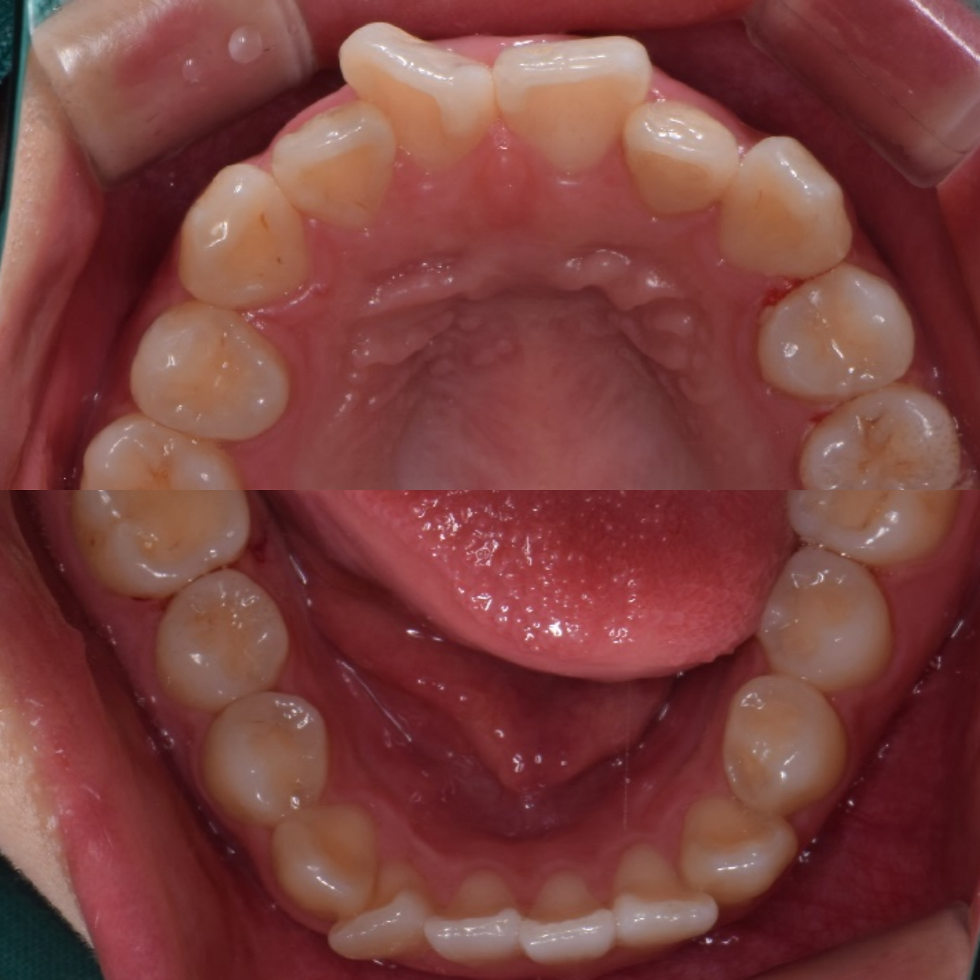

치아들의 뻐드러짐이 심하고, 공간이 너무 부족해 보여요. 발치교정까지도 고려해야되는 상황인데, 저는 발치교정을 그다지 좋아하지 않아서, 고민이 많이 되는 케이스였어요. 환자의 나이가 아직 20살이 되지 않았기 때문에, 구개확장장치를 써서 치아가 배열될 공간을 늘려주고, 치열을 배열하면, 좀 좋아지지 않을까 싶어서, 미니튜브와 구개확장장치를 사용해서 교정을 하기로 했어요.

5개월 뒤, 미니튜브와 구개확장장치로 인해 치아가 배열이 될 충분한 공간마련과 배열이 어느정도 끝났어요. 구개확장장치를 제거했고, 위의 치아의 경우 약간 왼쪽 송곳니와 작은 어금니가 바깥쪽으로 배열된 부분이 있는데, 이건 투명교정으로 마무리하기로 했어요.

4개월 정도의 투명교정과 아래 교정 마무리 과정을 통해, 발치교정으로 갈 수도 있었던 케이스를 1년도 안되는 기간만에 빠르고 편안하게 끝낼 수 있었어요. 환자 분의 만족도도 최상이었고요. 빠르고 편안함, 저희 에어라인 교정의 특징이라고도 할 수 있겠습니다. 감사합니다.